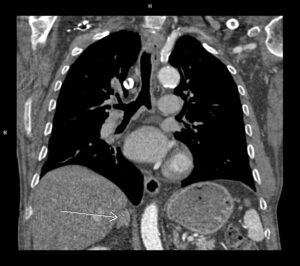

Video 2: reconstrucție coronală din achiziție de volum CT postcontrast abdomen superior la un pacient cu icter

Discuţie caz nr 60: Pacientul a efectuat examinare CT de urgență pentru sindrom icteric; la examinarea CT s-a pus în evidența creștere de calibru a căilor biliare bilateral cu aspect simetric cu decalibrare în hilul hepatic unde se pune în evidență o leziune densă, slab iodofilă; s-a recomandat completare cu examinare IRM. Examinarea IRM a evidențiat un colangiocarcinom periductal infiltrativ – tumoră Klatskin ce evoluează și la nivelul ductului cistic și la nivelul coledocului în jumătatea proximală (săgeți). Deasemenea, atât la examinarea CT cât și la examinarea IRM se pune în evidență creștere difuză a grosimii peretelui gastric ce este hipokinetic cu adenopatii perigastrice – endoscopia digestivă efectuată cu prelevare de biopsii a pus diagnosticul de limfom gastric infiltrativ sincron.

DE LUAT ACASĂ!!! Creșterea difuză sau localizată de calibru a cailor biliare la eco sau CT sugerează indicația de examinare IRM pentru caracterizare tisulară suplimentară a obstacolului: litiază sau leziune expansivă. Examinarea ultrasonografică este 100% fiabilă în diagnosticul litiazei biliare veziculare sau de căi biliare în cazul unui utilizator experimentat. Leziunile expansive de căi biliare sunt în general caracterizate prin IRM cu ajutorul achizițiilor T1 pre și postcontrast și de difuzie, iar achizițiile T2 ajută la localizare prin evidențierea locului de decalibrare a cailor biliare.